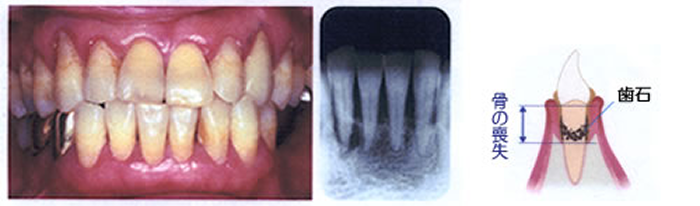

中等度歯周炎

歯周ポケットが形成され、歯石が深部まで付着し歯を支える骨を半分くらい失っています。